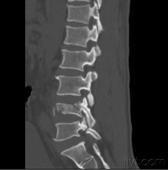

由多個運動節段組成的脊柱,在遭受過度的運動或外力時即可引起損傷。致傷暴力包括過度的前屈、后伸、擠壓、分離、剪切和旋轉力等,凡超過生理極限即可引起損傷。

按照Denis三柱概念,爆裂骨折已成為脊柱骨折中具有重要臨床意義的一型,如處理不當,易引起意外。

Denis等人強調,當椎體的后壁和后部纖維環等結構,即包括后縱韌帶的中柱一旦遭受破壞,則可造成前屈狀態下的不穩定,并把此種累及前柱和中柱的骨折定義為爆裂骨折。